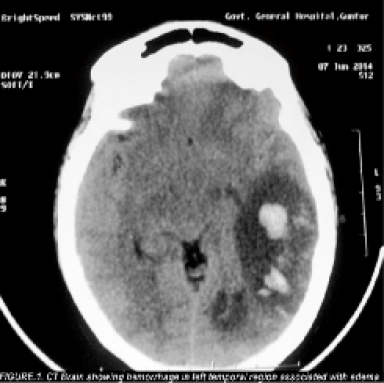

A young unmarried female presented with history of high grade fever of two days duration associated with head ache, vomiting, reeling sensation followed by delirium and seizures after roaming in a very hot summer day. Before getting admitted in the hospital she was treated with cold and wet blankets, intravenous fluids and antipyretics for one day . There was no history of any significant illness. She was not on any medication. On examination, patient was afebrile, drowsy and incoherent. Headache and vomiting are present. There were no signs of meningeal irritation or focal neurological deficits. Papilloedema was present. Her blood sugar, renal and liver function tests and electrolytes were within normal limits. Pregnancy test was negative and urine examination was normal. Computerised Tomogram of brain [Figure: 1] revealed hemorrhage in left temporal region associated with edema. Magnetic resonance scan of brain [Figure:2&3] showed hemorrhagic infarct in the left temporal region and thrombus in the left transverse and sigmoid sinus. Her connective tissue profile was normal (Antiphospholipid antibodies, Antinuclear antibodies, Anti ds-DNA were negative and, Protein C, Protein S, AntiThrombin III and Homocysteine were within normal limits).

- CT Brain showing hemorrhage in left temporal region associated with edema.